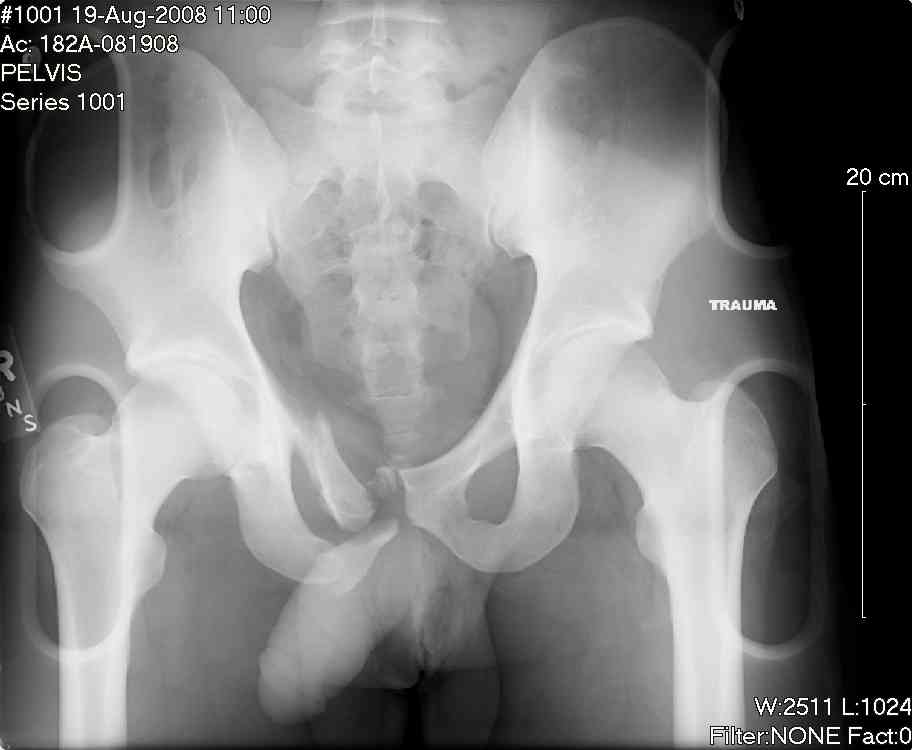

this is a healthy 22yo male. peds vs auto.

no other injuries. has anyone treated these non-operatively? thanks.